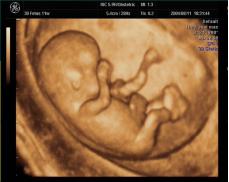

随着宝宝在妈妈肚子里一天天长大,准妈妈渴望知道宝宝在妈妈肚子里的情况,宝宝在里面什么样子?现在,三维彩超可以让你如愿以偿。

海宁康华医院引进飞利浦、GE高端彩超设备,开展胎儿三维超声检查,能够立体显示出宝宝在子宫中的实时图像,观察胎儿的生长发育情况,让每一位准妈妈尽早感受到为人母的幸福和喜悦。

胎儿三维超声检查的最佳时间:

22—24周(双胎不做三维超声检查)